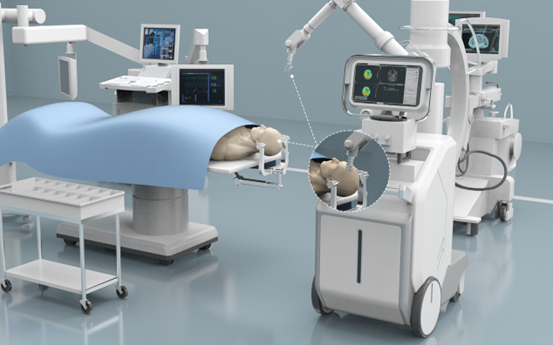

目前,就脑机接口芯片而言,由马斯克的Neuralink公司研制的脑机接口芯片N1采用的是单芯片256通道,同时采用常规芯片封装,只能通过引线进行连接;而衷华脑机研发的这款植入式脑机接口系统的神经测量调控芯片所采用的是单芯片2048通道,还支持双向神经信号测量调控的技术,不仅可以读取大脑信号,还可以向大脑发送信号。举个例子,未来四肢瘫痪患者植入了该脑机接口系统后,可以读取大脑的神经活动来控制机械手,与此同时,机械手上的传感器能将机械力等通过皮层内微模拟传回到大脑感觉皮层,让患者拥有触觉感觉,就像是真的手臂一样。

据悉,衷华脑机已研制出百余种的微针,从单柄、多柄微针到数万个通道的阵列型微针。这些微针既可以用于人脑,也可以用于脊椎、眼球、四肢或腹腔内各个脏器。首席科学家黄立表示,衷华脑机希望能够借助研发的全自动手术机器人为植入类手术提供一整套高精度、全自动化解决方案。

据悉,衷华脑机形成了一套包含植入式微针、超高速数据传输系统、海量数据处理平台以及植入设备的一站式植入式脑机接口系统。这一整套高精度、全自动化解决方案为脑科学研究与神经疾病诊疗提供了科学的手段和方法。